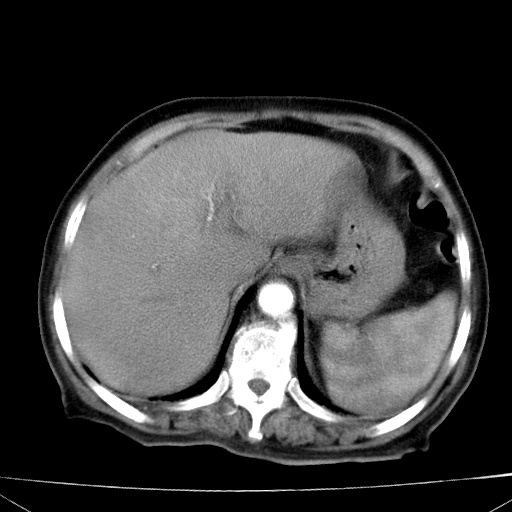

网站人气太旺!昨天的帖子就沉到海底,只好再发贴!ct18338:女 78岁,肝胆病变,已增强,再会诊!原帖链接:http://www.radida.com/bbs/forum.php?mod=viewthread&tid=50032

1)考虑胆囊癌侵犯肝脏并肝门区、腹膜后及右侧膈角后淋巴结转移。2)肝左叶近肝顶部囊肿。3)肝左叶肝内胆管结石。4)左肾近下极囊肿。